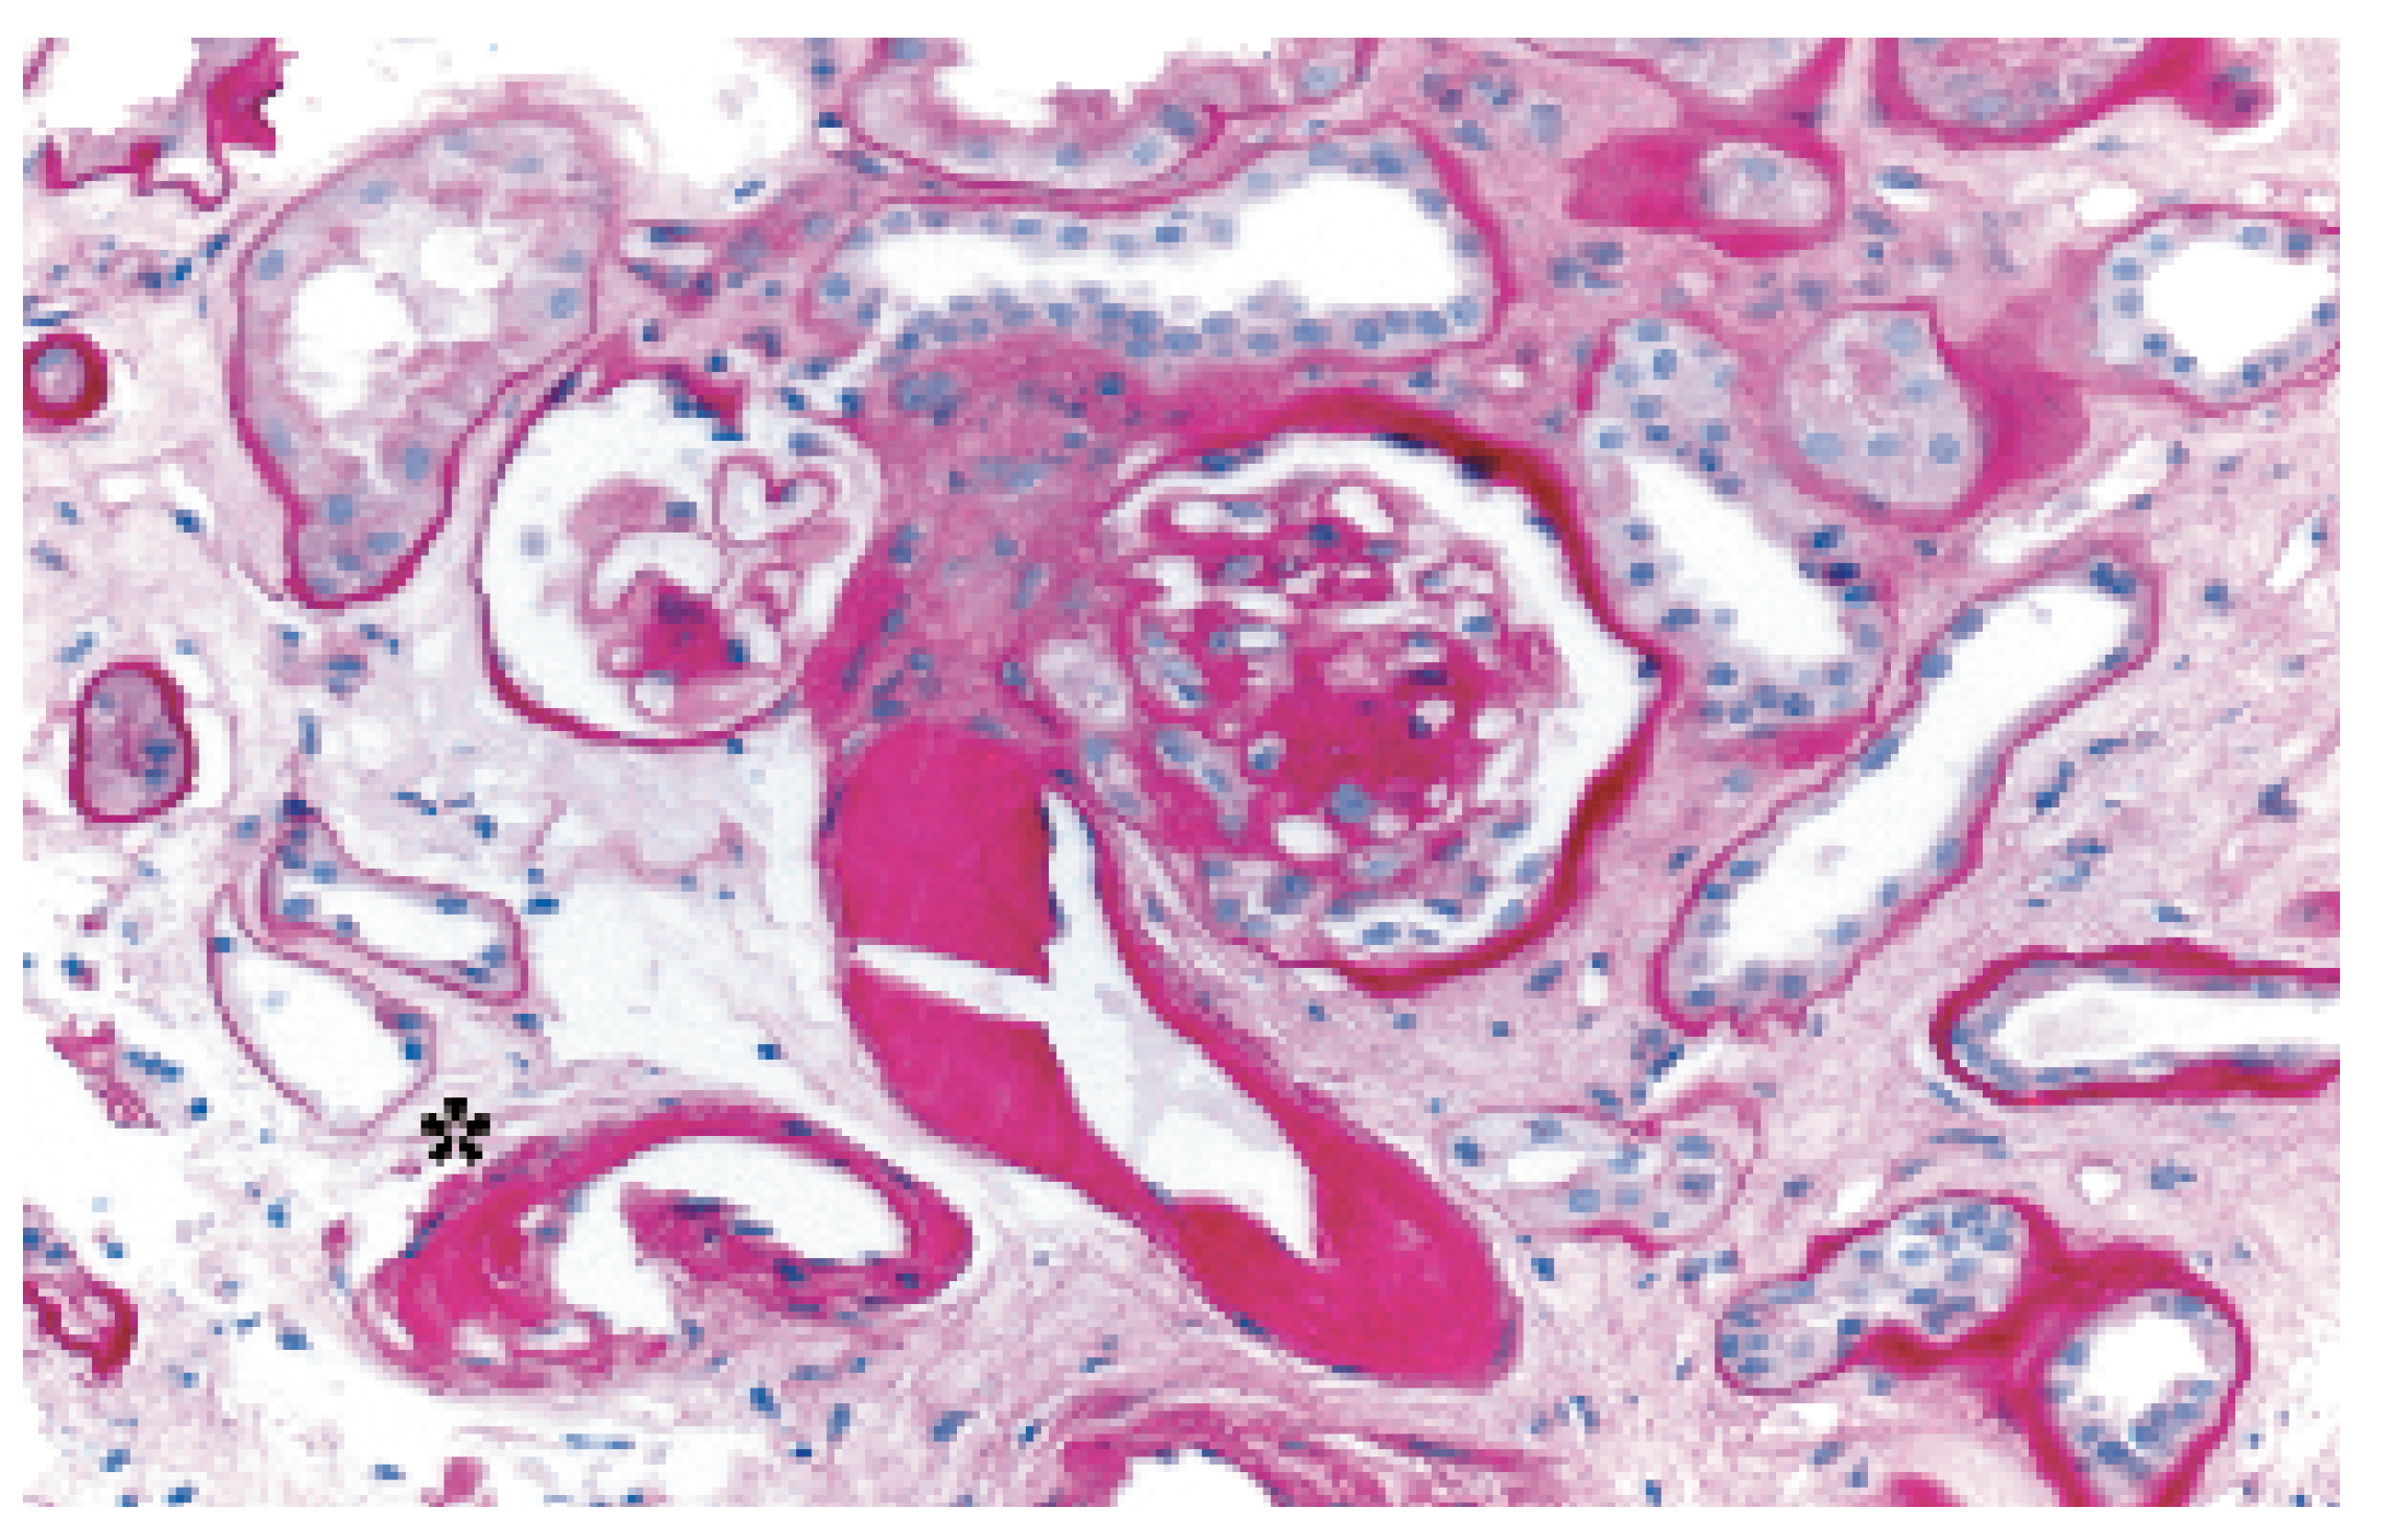

On September 23rd, 1985, a 34-year-old man with end-stage dilated cardiomyopathy of unknown origin and with history of severe dyspnea (NYHA III–IV) during the preceding five years underwent orthotopic heart transplantation (HTX). Left ventricular ejection fraction (EF) before HTX was 20%. Immunosuppression included cyclosporine A, azathioprine and prednisone. Acute cellular rejections occurred 14, 49 and 70 days after HTX. Six months after HTX the patient returned to full work as a farmer. The long follow-up was characterised by excellent quality of life, the lack of further rejections, severe infections and of secondary tumors. Twenty years after HTX, selective coronary angiography and intravascular ultrasound (IVUS) showed only mild coronary stenoses (Figure 1) associated either to de novo atherosclerotic lesions and/or graft vasculopathy. This surprisingly mild vasculopathy may be due to the excellent match (two HLA missmatch) with few cellular rejections in the very early course after HTX. EF was normal (60%). The major issue during follow-up was the appearance of moderate to severe renal function impairment probably related to a side effect of cyclosporine. Mild renal function impairment occurred few months after HTX with progressive severe deterioration of the creatinine clearance down to 27 ml/min/m2 twenty years after HTX. Renal biopsy, performed 20 years after HTX, showed typical changes with arteriolopathy characteristic for calcineurin inhibitor toxicity (cyclosporine) (Figure 2). This case illustrates how long-term survival after HTX is possible with excellent quality of life with only mild coronary vasculopathy and moderate to severe renal insufficiency.

Figure 2. Figure 2 shows renal biopsy, performed twenty years after HTX, indicating arteriolopathy characteristic for calcineurin inhibitor toxicity (cyclosporine) (*). It also shows severe unspecific arteriolopathy and a glomerulus with increase of mesangial matrix.